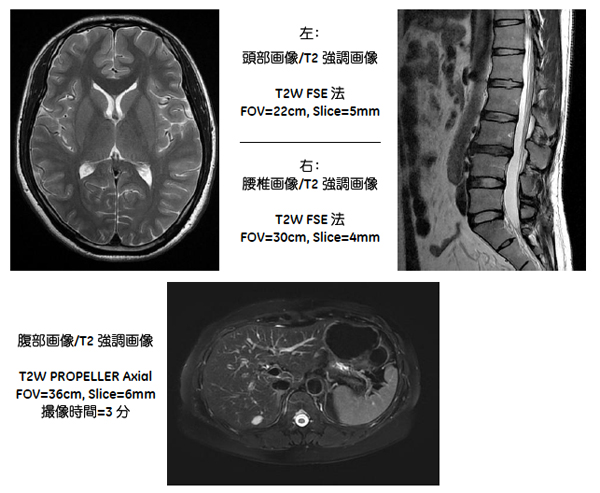

Brivo MR355 Inspire 1.5T搭載の主要アプリケーションを使用した撮影画像

アーチファクト(偽像)につながる検査中の患者さんの動きを高度に補正し,再撮像の機会を低減する「PROPELLER(プロペラ)」や造影剤を使用しない血管撮像ソフトウエア 「InhanceSuite(インハンス・スイート)」など先進アプリケーションを搭載。患者さんの負担の少ないMRI検査を実現する。